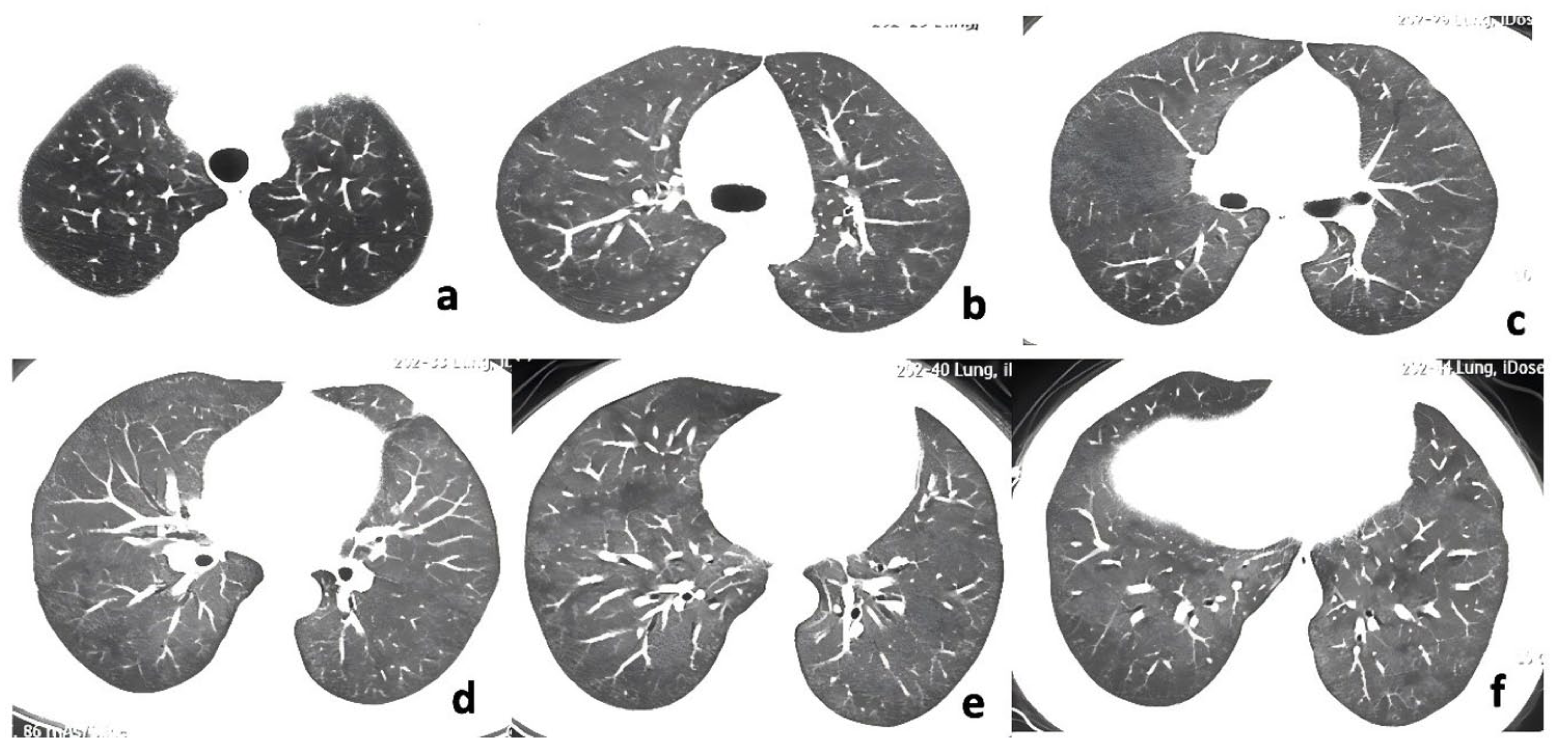

On December16, 2021, a 51-year-old female hairdresser with 20-year occupational exposure to hair dyes and no history of smoking came to our department for treatment. She presented with a 6-month history of non-productive cough, progressive exertional dyspnea, and a weight loss of 7 kg, which was classified as Modified Medical Research Council (mMRC) grade 2 (Figure 1). She has no symptoms of xerostomia or dry eyes, and physical examination revealed no Gottron’s sign, V-sign, arthralgia, or myasthenia. Previously, she had visited the community hospital multiple times due to persistent dry cough and was misdiagnosed with chronic bronchitis in May 2021. After taking the dextromethorphan tablets as prescribed by the doctor, her condition did not improve. On August 13, 2021, she began to experience shortness of breath after physical activity, which gradually worsened. Laboratory examination revealed a diffusion capacity of the lungs for carbon monoxide (DLCO) of 3.58 mL/min/mmHg (46.1% predicted). HRCT demonstrated diffuse bilateral involvement with GGOs (Figure 2(a)–(f)). Based on occupational organic compound exposure and imaging findings, she was misdiagnosed with non-fibrotic hypersensitivity pneumonitis (HP) and treated with prednisone (30 mg/day), showing partial improvement (mMRC grade 1) after 2 weeks. However, her dyspnea worsened to mMRC grade 3 with saturation of peripheral oxygen (SpO2) dropping to 85% as prednisone was tapered to 15 mg/day. Consequently, she was admitted to our hospital for further treatment this time.

The HRCT of the chest of the patient on August 13, 2021.

The day after admission, laboratory investigations revealed pancytopenia with leukocyte count 1.92 × 109/L (neutrophils 1.13 × 109/L, lymphocytes 0.56 × 109/L), anemia (hemoglobin 102 g/L), and thrombocytopenia (84 × 109/L). Liver, cardiac, and renal function tests showed no abnormalities. Sputum bacterial and fungal smears showed no pathogenic microorganisms. Elevated inflammatory markers included D-dimer (596 ng/mL), lactate dehydrogenase (LDH, 1055.6 U/L), and ferritin (522.4 ng/mL). The level of serum interleukin-10 (IL-10) rose to 153.70 pg/mL. Autoimmune serology revealed positive antinuclear antibodies with a cytoplasmic granular pattern (titer 1:320) and elevated myositis-specific anti-SRP antibodies (+++). Serum krebs von den lungen-6 (KL-6) was elevated at 670 U/mL. Chest CT revealed diffuse GGOs with peribronchiolar distribution and adjacent consolidation in both lungs (Figure 3(a)–(f)). Pulmonary function testing demonstrated significantly impaired gas exchange capacity with DLCO at 39.4% predicted on December 17, 2021.

The HRCT of the chest of the patient on December 17, 2021.